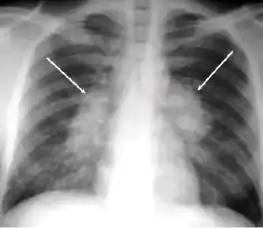

2. Any cavitary lesion - Lucency (darkened area) within the lung parenchyma, with or without irregular margins that might be surrounded by an area of airspace consolidation or infiltrates, or by nodular or fibrotic (reticular) densities, or both. The walls surrounding the lucent area can be thick or thin. Calcification can exist around a cavity.

-

Chest X-ray of a person with advanced tuberculosis: Infection in both lungs is marked by white arrow-heads, and the formation of a cavity is marked by black arrows.